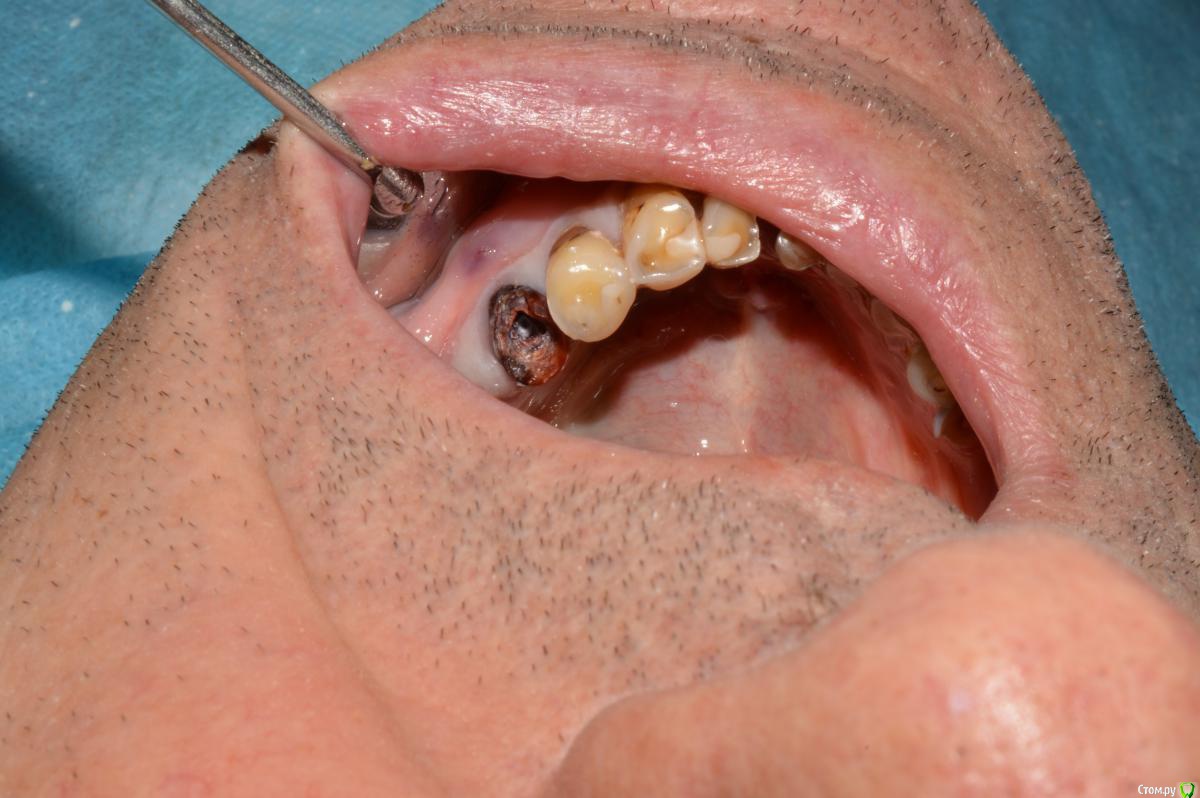

Елена509 Опубликовано 19 ноября, 2015 Поделиться Опубликовано 19 ноября, 2015 Доктора, помогите, пжл, ситуация какая - ортопед направил для удаления штифта и перепломбирования к.к 35, начали - анестезия, выудили штифт, начали расширять, уперлись на 15 мм, пошли на снимок с гутт штифтом(прилагается), недолет, вернулись, сразу прошли дальше, по апексу -18мм, убавила до 17,5, мастер штифт - 35, латералка, пошли на контроль, а там - загнутый штифт за верхушкой(рг прилагается), вернулись, все вытащила, загнутый тоже(95% - я его прям признала), отмыли просушили, по апексу те же 18мм, примеряю мастер штифты все как то не так встает, в итоге 70 подогнала, на те же 17,5 мм, поставила, с латералкой, идем на контроль, там вот такая вот фигня(рг - "последний"), вопросы - это что, невытащеннный гут.штифт или на его место эпоксидка затекла? что с прогнозом и что делать? 1 Ссылка на комментарий

Сева северный Опубликовано 19 ноября, 2015 Поделиться Опубликовано 19 ноября, 2015 (изменено) перед тем, как пошли делать с гут.штифтом рг недолет показывал, вроде нормально все было, когда пломбировали, штифты тоже никуда не уходили на месте стояли, я даже как то растерялась сильно, когда на контрольном на столько за апекс ушлисудя по фото....зуб резарцинен..... с дефектом твердых тканей( это диазноз)..ферол наверное отсутствует. Чтобы было понятно ......лечение резарциненого зуба с таким разрушением..+ осложненным необходимостью эндолечения .... является альтернативой удалению.Что касается :Что за верхушкой ?.... Границы четкие, если вынули гуту ....крючком.... для себя считайте силер..даже если и гута связь с каналом зуба отсутствует. поэтому реакция будет либо незначительная , либо отсутствовать вообще. Прогноз по зубу, строил бы из ортопедической целесообразности.... Изменено 19 ноября, 2015 пользователем Сева северный 1 Ссылка на комментарий

kozloff Опубликовано 20 ноября, 2015 Поделиться Опубликовано 20 ноября, 2015 Между прочим зуб на удаление Ссылка на комментарий

Sampson Опубликовано 21 ноября, 2015 Поделиться Опубликовано 21 ноября, 2015 Резорциненный+пародонтитный+ изменения апекальной трети корня+ тень материала за верхушкой = Я бы зуб пока сохранил в целях наблюдения. и раз в неделю проводил перкуссию. При положительной динамике отправил к ортопеду. При отрицательной к хирургу. Ссылка на комментарий